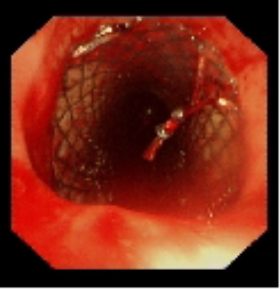

术中植入金属覆膜支架